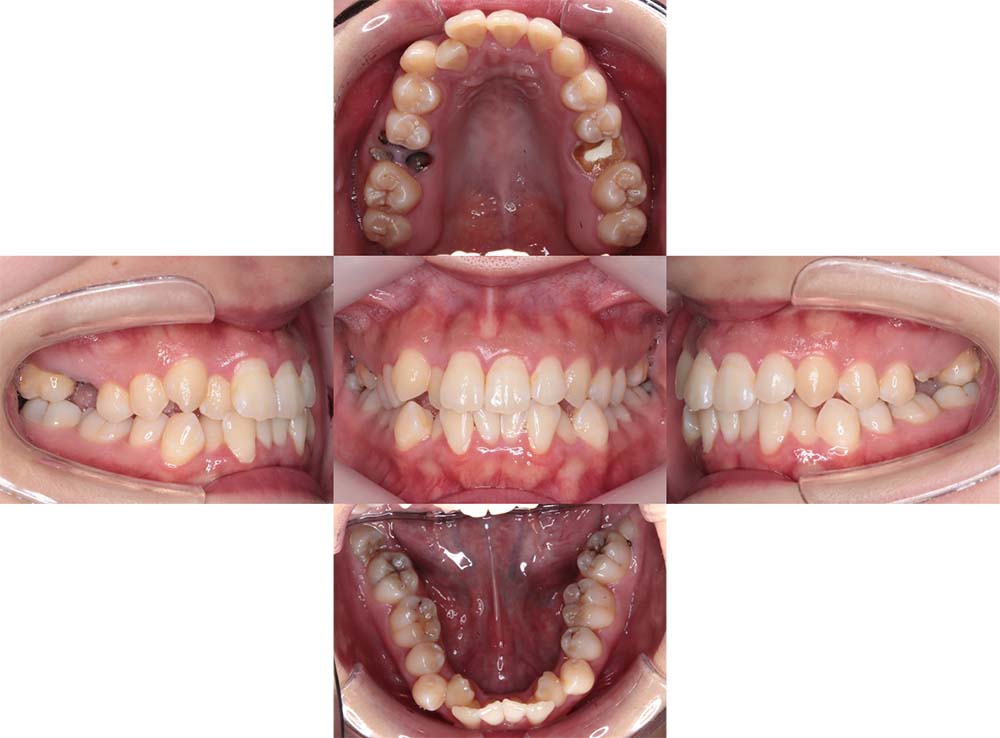

症例04

| 主訴 | 歯並びのガタガタと出っ歯が気になる。 |

| 診断名あるいは主な症状 | 上顎前突、叢生 |

| 年齢/性別 | 16歳・女性 |

| 矯正ステージ | 大人の矯正治療 |

| 治療方法 | ワイヤー矯正 |

| 抜歯部位/抜歯有無 | 抜歯 |

| 治療内容 | 抜歯したスペースを使用し、ガタガタの改善と上下顎前歯を後退させた。 |

| 費用 |

85万円程度(2025.10時点の料金となります。) ※矯正基本料金、審美ブラケットを含む |

| 治療期間 | 2年5ヶ月 |

| 主なリスク・副作用 | 痛み、歯根吸収、歯肉退縮、虫歯、後戻り |